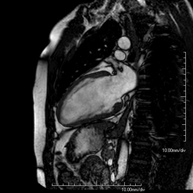

- RM Cardíaca

És una prova diagnòstica no invasiva que obté informació morfològica i funcional del cor i les estructures adjacents. D'aquesta manera es poden diagnosticar diferents patologies congènites i adquirides i realitzar controls en pacients amb patologia prèvia ja coneguda. En la majoria de casos és necessari l'ús de contrast intravenós (Gadolini) per completar l'estudi, un tipus de contrast que estranyament produeix reaccions adverses. Durant la prova el tècnic li demanarà diverses vegades que aguanti la respiració durant 10-15 segons per obtenir les imatges el més clares possible. No requereix preparació prèvia per part del pacient. La durada de la prova és d'aproximadament 45-60 minuts. Està contraindicada en pacients amb marcapassos i el pacient ha d'indicar si és portador d'implants metàl·lics i/o clips quirúrgics. - RM Cardíaca amb estrès miocàrdic

És una prova diagnòstica no invasiva que obté informació morfològica i funcional del cor i les estructures adjacents. D'aquesta manera es poden diagnosticar diferents patologies congènites i adquirides. Durant la prova el tècnic li demanarà diverses vegades que aguanti la respiració durant 10-15 segons per poder obtenir les imatges el més clares possible. En la gran majoria de casos és necessari l'ús de contrast intravenós (Gadolini) per completar l'estudi, un tipus de contrast que rarament produeix reaccions adverses. A més, s'introdueix un fàrmac (Adenosina) per via intravenosa, per exercir sobre el cor un efecte similar al que es produeix durant l'exercici físic. Es comparen les imatges obtingudes en repòs i després de "l'estrès" farmacològic per detectar dèficits d'aportació sanguini al ventricle esquerre del cor. La durada de la prova és d'aproximadament 45-60 minuts. El pacient no haurà d'ingerir aliments que continguin cafeïna durant les 24 hores prèvies a prova (cafè, te, xocolata, begudes de cola, etc.). Està contraindicada en pacients amb marcapassos i el pacient ha d'avisar si és portador d'implants metàl·lics i/o clips quirúrgics. - Angio-RM de Venes pulmonars